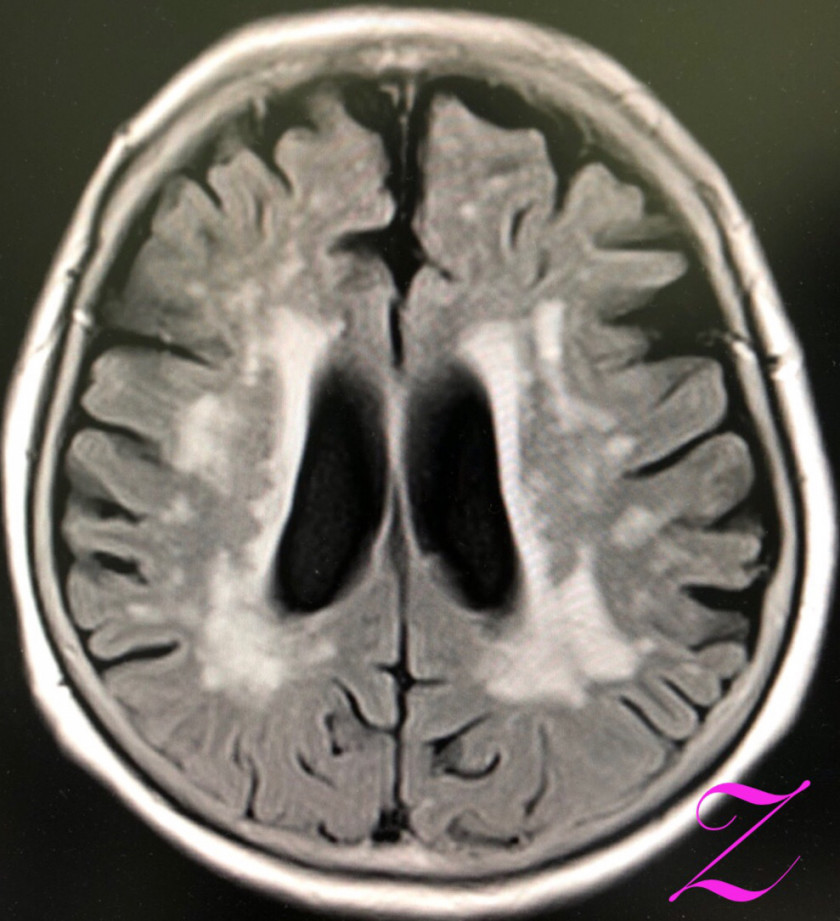

2018/09/18 MRIでも◯◯だから、CTなんて❌❌

今回、ちょっとしたキッカケがあり、MRI撮影となりました。認知機能に問題なく、年に何回か(つい最近も)、海外に一人で行って来る方。長年の高血圧もあり、降圧剤を処方していますが、コントロール状況は良好。でも、最近の言動は昔より、何だか、自己否定的。鬱っぽい・・・。もともと、アタマの回転の良い方。御両親も、お子様も医療関係者。

色々な悩みも聞いてきたので、些細な言動でも、なんと無く気になる・・・。MRIの結果。前頭葉が萎縮している‼️

🤣まぁ、そんなことは全く心配していません。さて、ココから本題。CTファン❓には申し訳ないが、MRIの撮影条件は上記のモノだけではありません。

上と同じ部位を異なる条件で撮影したのが以下。

異常が一目瞭然。白い部分が目立ちます。いわゆる、白質病変ですね。MRIを撮影しても、最初の条件のモノでは、診断できませんでした。では、CTだったら診断できましたか❓ゾッとしますね。各スライスをジッと見てみると、前頭葉の白質に白い部分が多いコトがわかりました。この所見は処方の参考にもなりました。なんとか、鬱っぽい状態から脱出させませんと。

もちろん、ノーサプリメントで。最後に。MRIでも完璧にはできないですが、CTで認知症診断なんてできますか❓

高血圧症例は可能な限り、MRI撮影をしてもらいましょう。